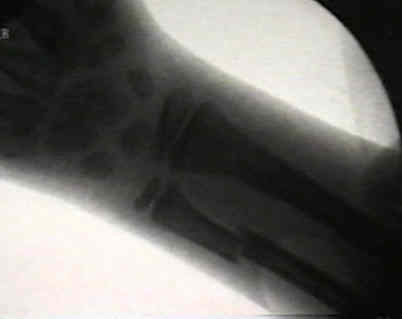

Displaced Distal Third Frx

- angulation up to 20-25 deg during first ten years is OK;

- angulation > 10 deg is unlikely to correct after 10 yrs